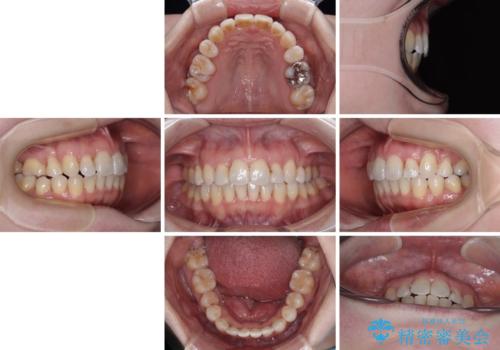

飛び出した上顎前歯と上下のデコボコ 片顎の抜歯によるワイヤー矯正

- 2年8ヶ月

- 30回以上

舌の突出癖が強く、治療途中で上下前歯が乖離した開咬となってしまいました。

舌のトレーニングで開咬は改善できますが、なかなかトレーニングが進まず、治療期間は想定よりも長期化してしまいました。